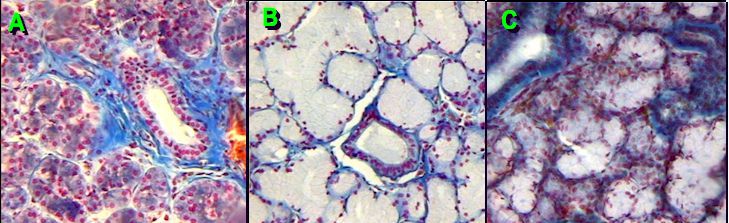

4. Identify A, B, C, D and E. in photo below.